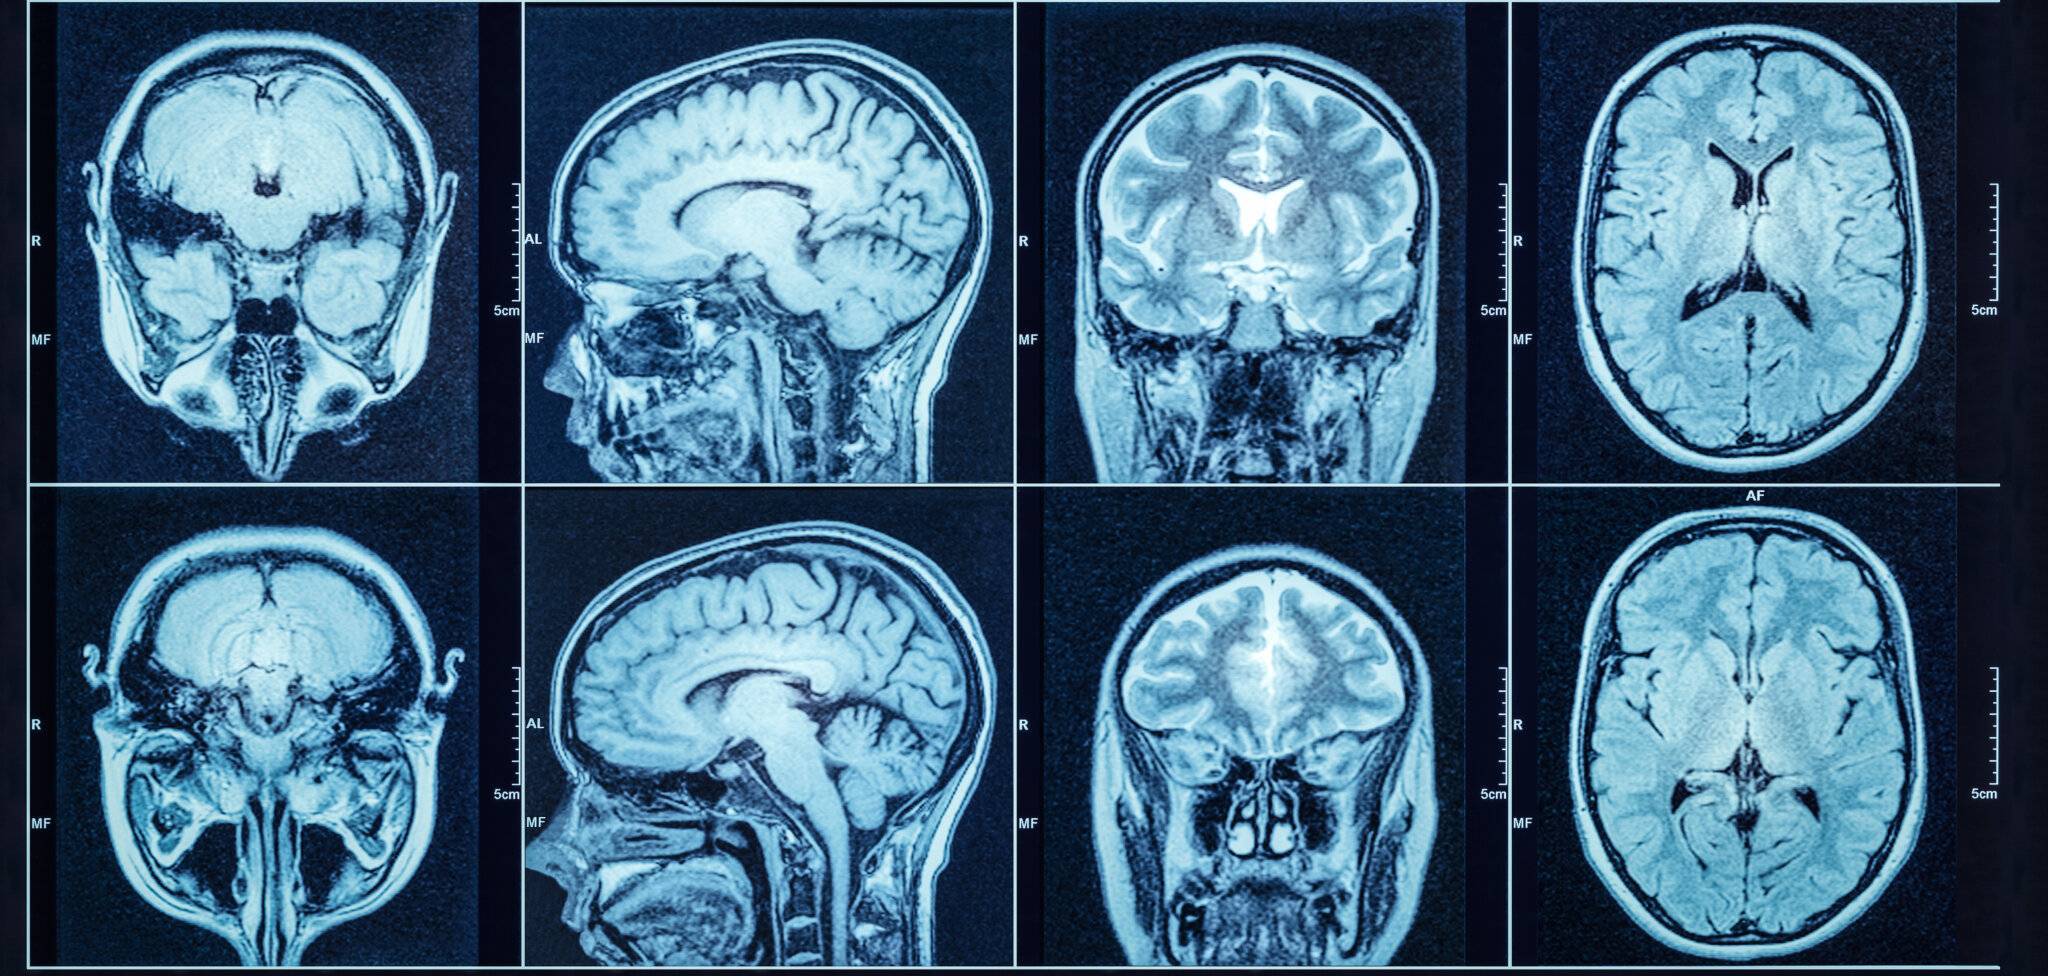

Ein CT-Scan, auch Computertomografie genannt, ist eine bildgebende Untersuchung, bei der mit Hilfe von Röntgenstrahlen und einem Computer detaillierte Bilder aus dem Körperinneren erstellt werden. Sie kann zur Diagnose verschiedener Zustände beitragen, von Verletzungen und Durchblutungsstörungen bis hin zu Krankheiten wie Krebs. Obwohl Organe und Gewebe auch auf Röntgenbildern zu sehen sind, neigen die Körperstrukturen dazu, sich zu überlappen, was ihre Unterscheidung erschwert. Deshalb empfehlen Ärzte CT-Scans anstelle von Röntgenbildern.

Anders als bei einer MRT-Untersuchung umschließt der CT-Scanner nicht den gesamten Körper des Patienten, so dass es für Menschen mit Platzangst einfacher sein kann, sich einer solchen Untersuchung zu unterziehen. (2) Sie müssen sich dennoch hinlegen und dürfen sich während des Scans nicht bewegen, damit sie qualitativ hochwertige Bilder erhalten.